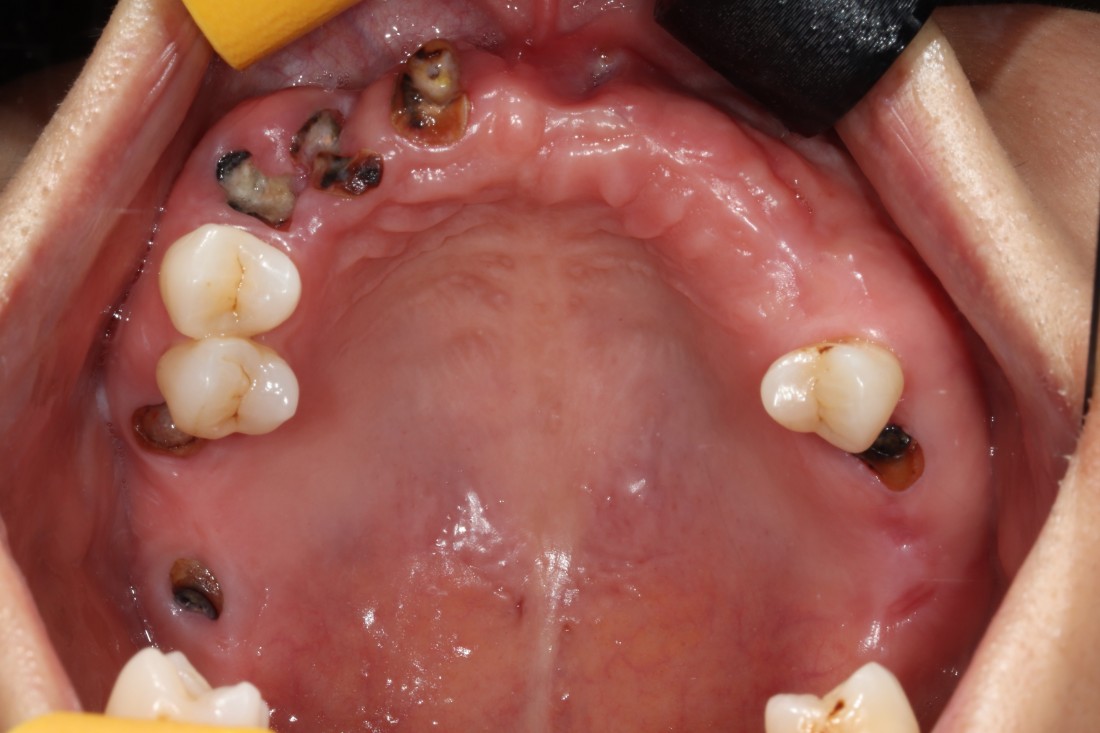

광주 상악임플란트 치과는

전체 임플란트 수술도

단 2번의 수술만으로

완성합니다.

우리가 치아를 나눌 때에

윗니 (상악) / 아랫니 (하악) 이렇게

간단하게 구분을 하는데요.

일반적으로 상악임플란트는

하악에 비해 잇몸뼈가 얇은 경우가 많고

예뻐야 하는 심미적인 부분도

담당하기 때문에

특별히 신경써서 상악임플란트 수술경험이

풍부한 구강외과 전문의에게

진료받는 것을 추천드립니다.

광주 상악임플란트 치과에서는

위 / 아래 전체 임플란트를

붓기, 출혈, 통증을 최소화할 수 있는

디지털 가이드 임플란트 수술방법으로

단 2번의 수술만으로 완성하고 있습니다.